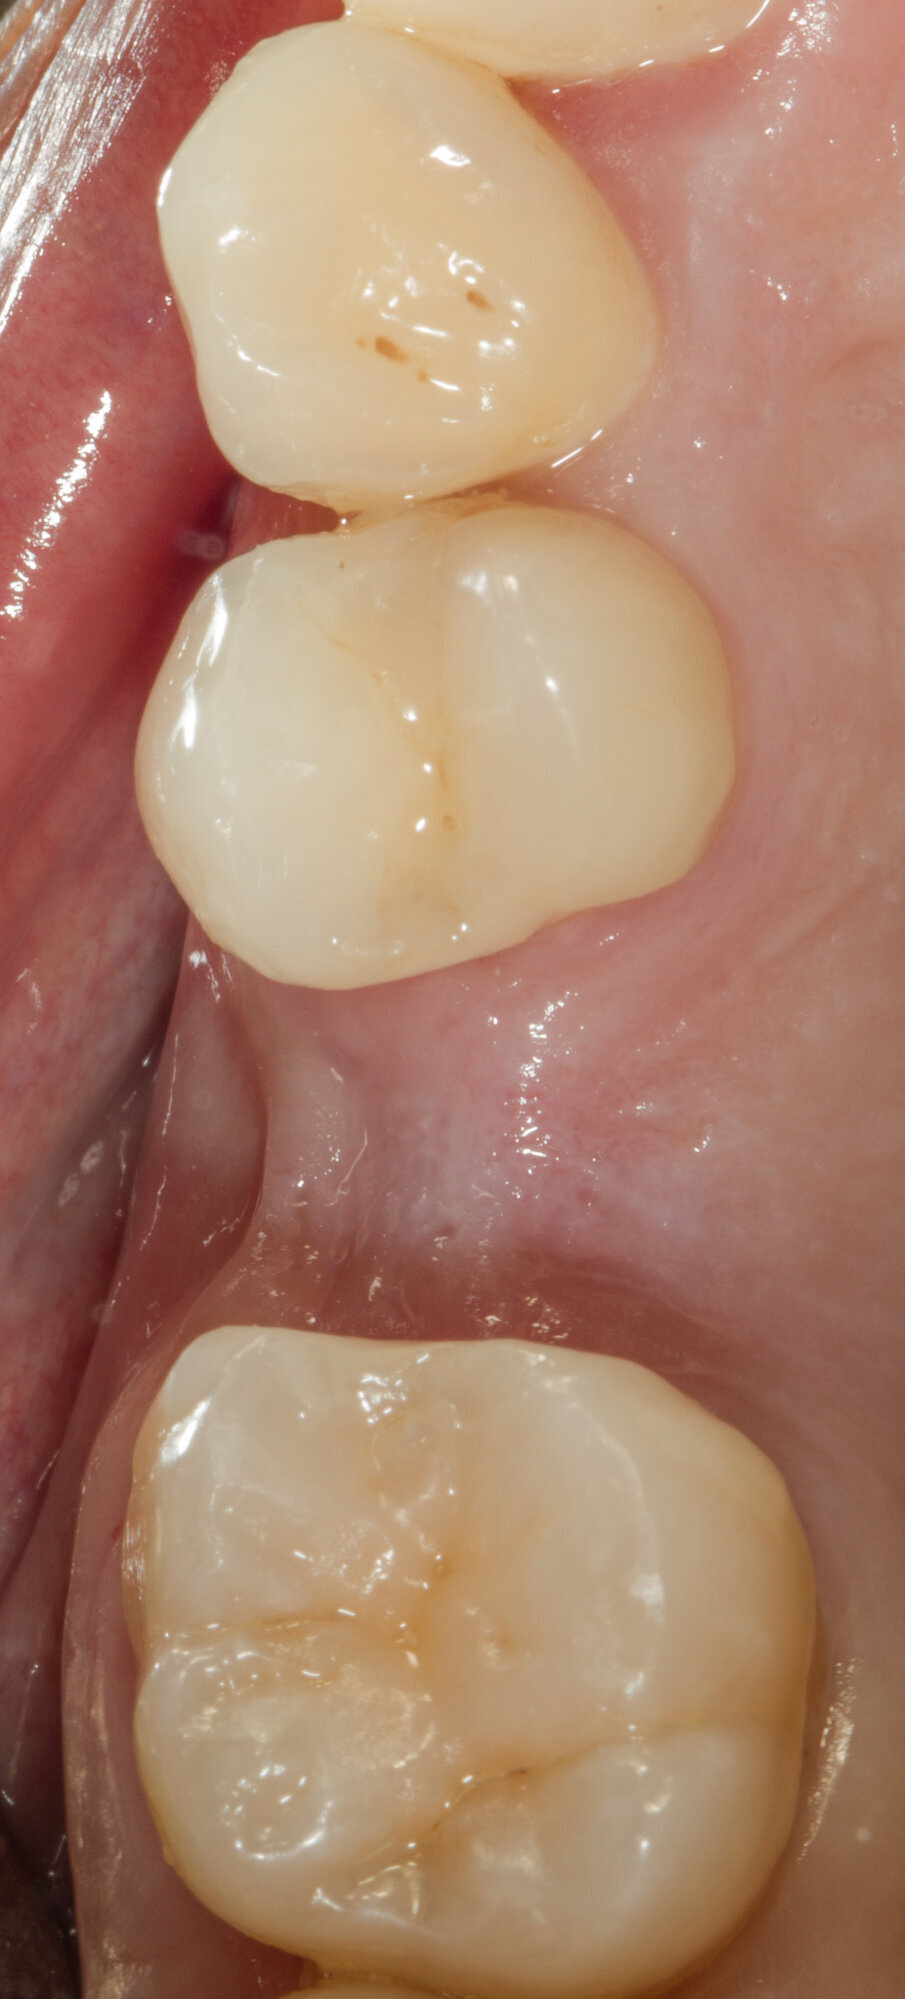

Viene inserito nel centro della cresta neoformata un impianto osteointegrato Neoss Tapered 4.0 x 13 mm con torque di inserimento di 60 Ncm e ISQ 80 (Figg. 22-24). La rigenerazione ossea crestale permette di inserire l’impianto in una posizione protesicamente guidata e con 2 mm di tessuto osseo vestibolare; questa situazione migliora la prevedibilità della riabilitazione implanto-protesica29-33. Dopo 2 mesi di provvisorizzazione si cementa il manufatto protesico definitivo (Figg. 25-28). Il controllo clinico e radiologico a 6 anni (Figg. 29, 30) mostra la stabilità dei tessuti molli e dell’osso perimplantare. Il confronto tra baseline e 6 anni dalla riabilitazione protesica evidenzia la stabilità nel tempo della rigenerazione volumetrica crestale (Fig. 31).

Fig. 27 - Corona protesica definitiva cementata.

Fig. 29 - Controllo clinico a 6 anni.